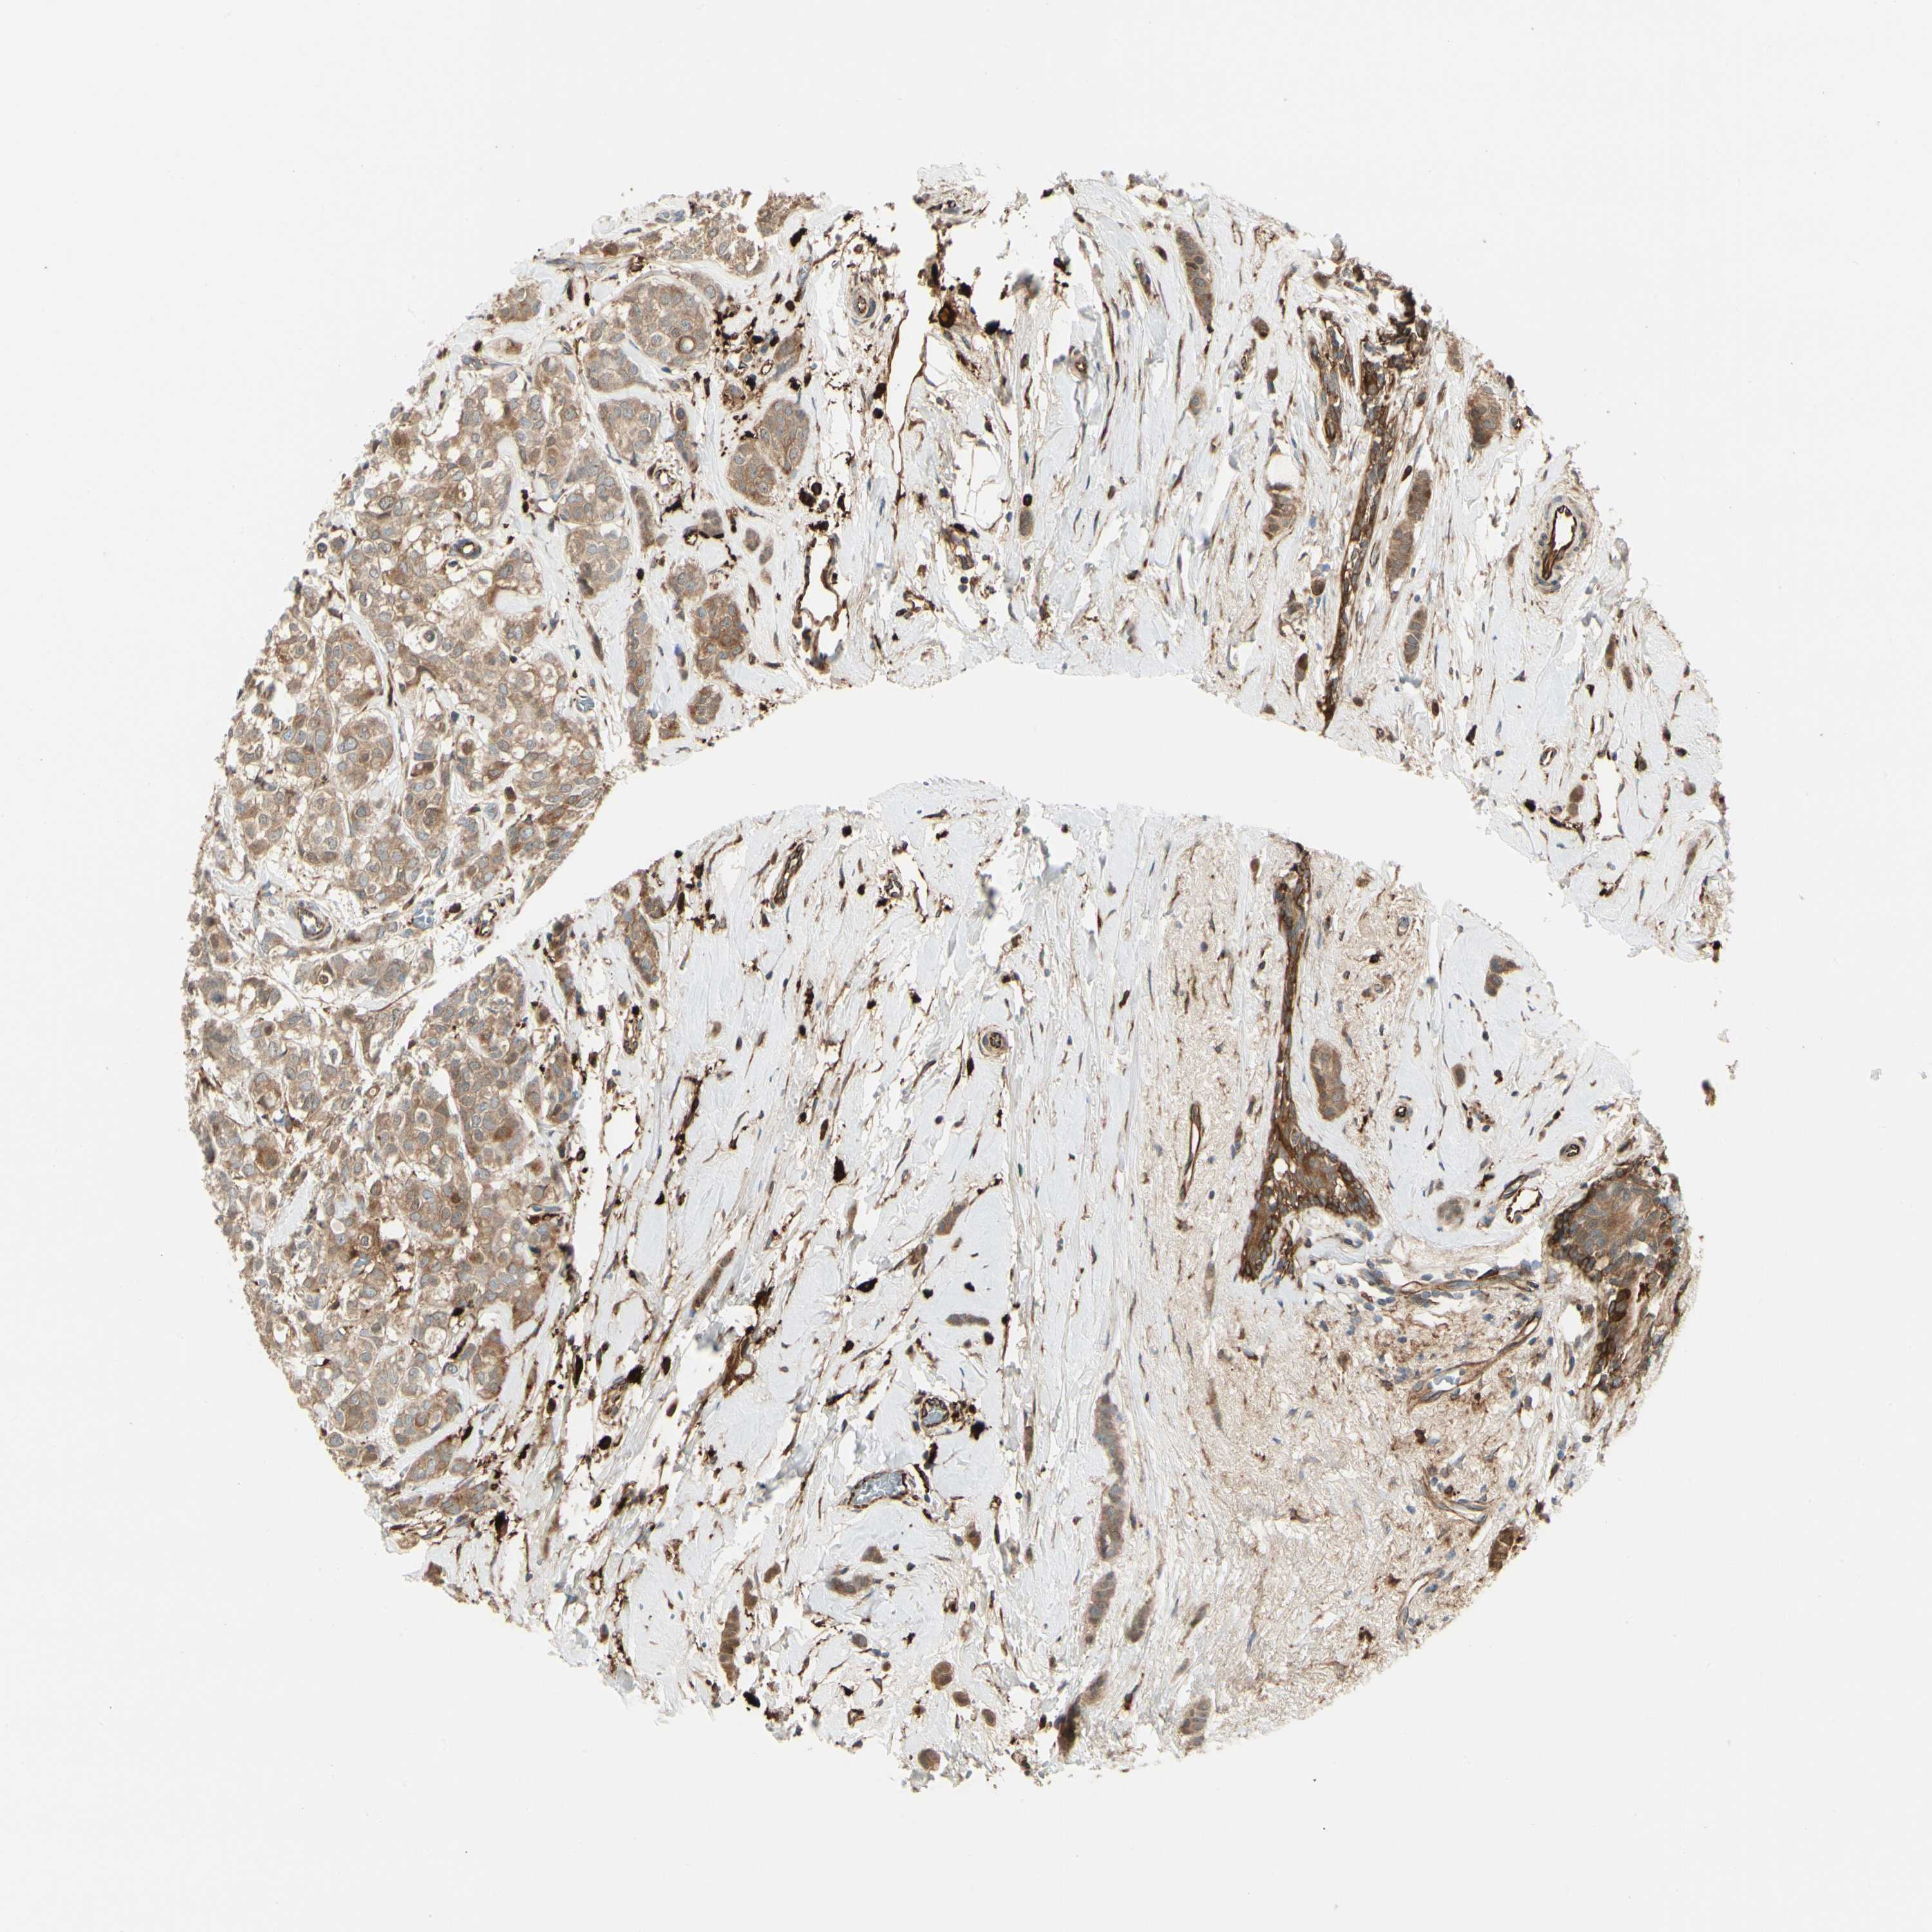

BRCA TCGA BRCA VALIDATION PROTEIN EXPRESSION